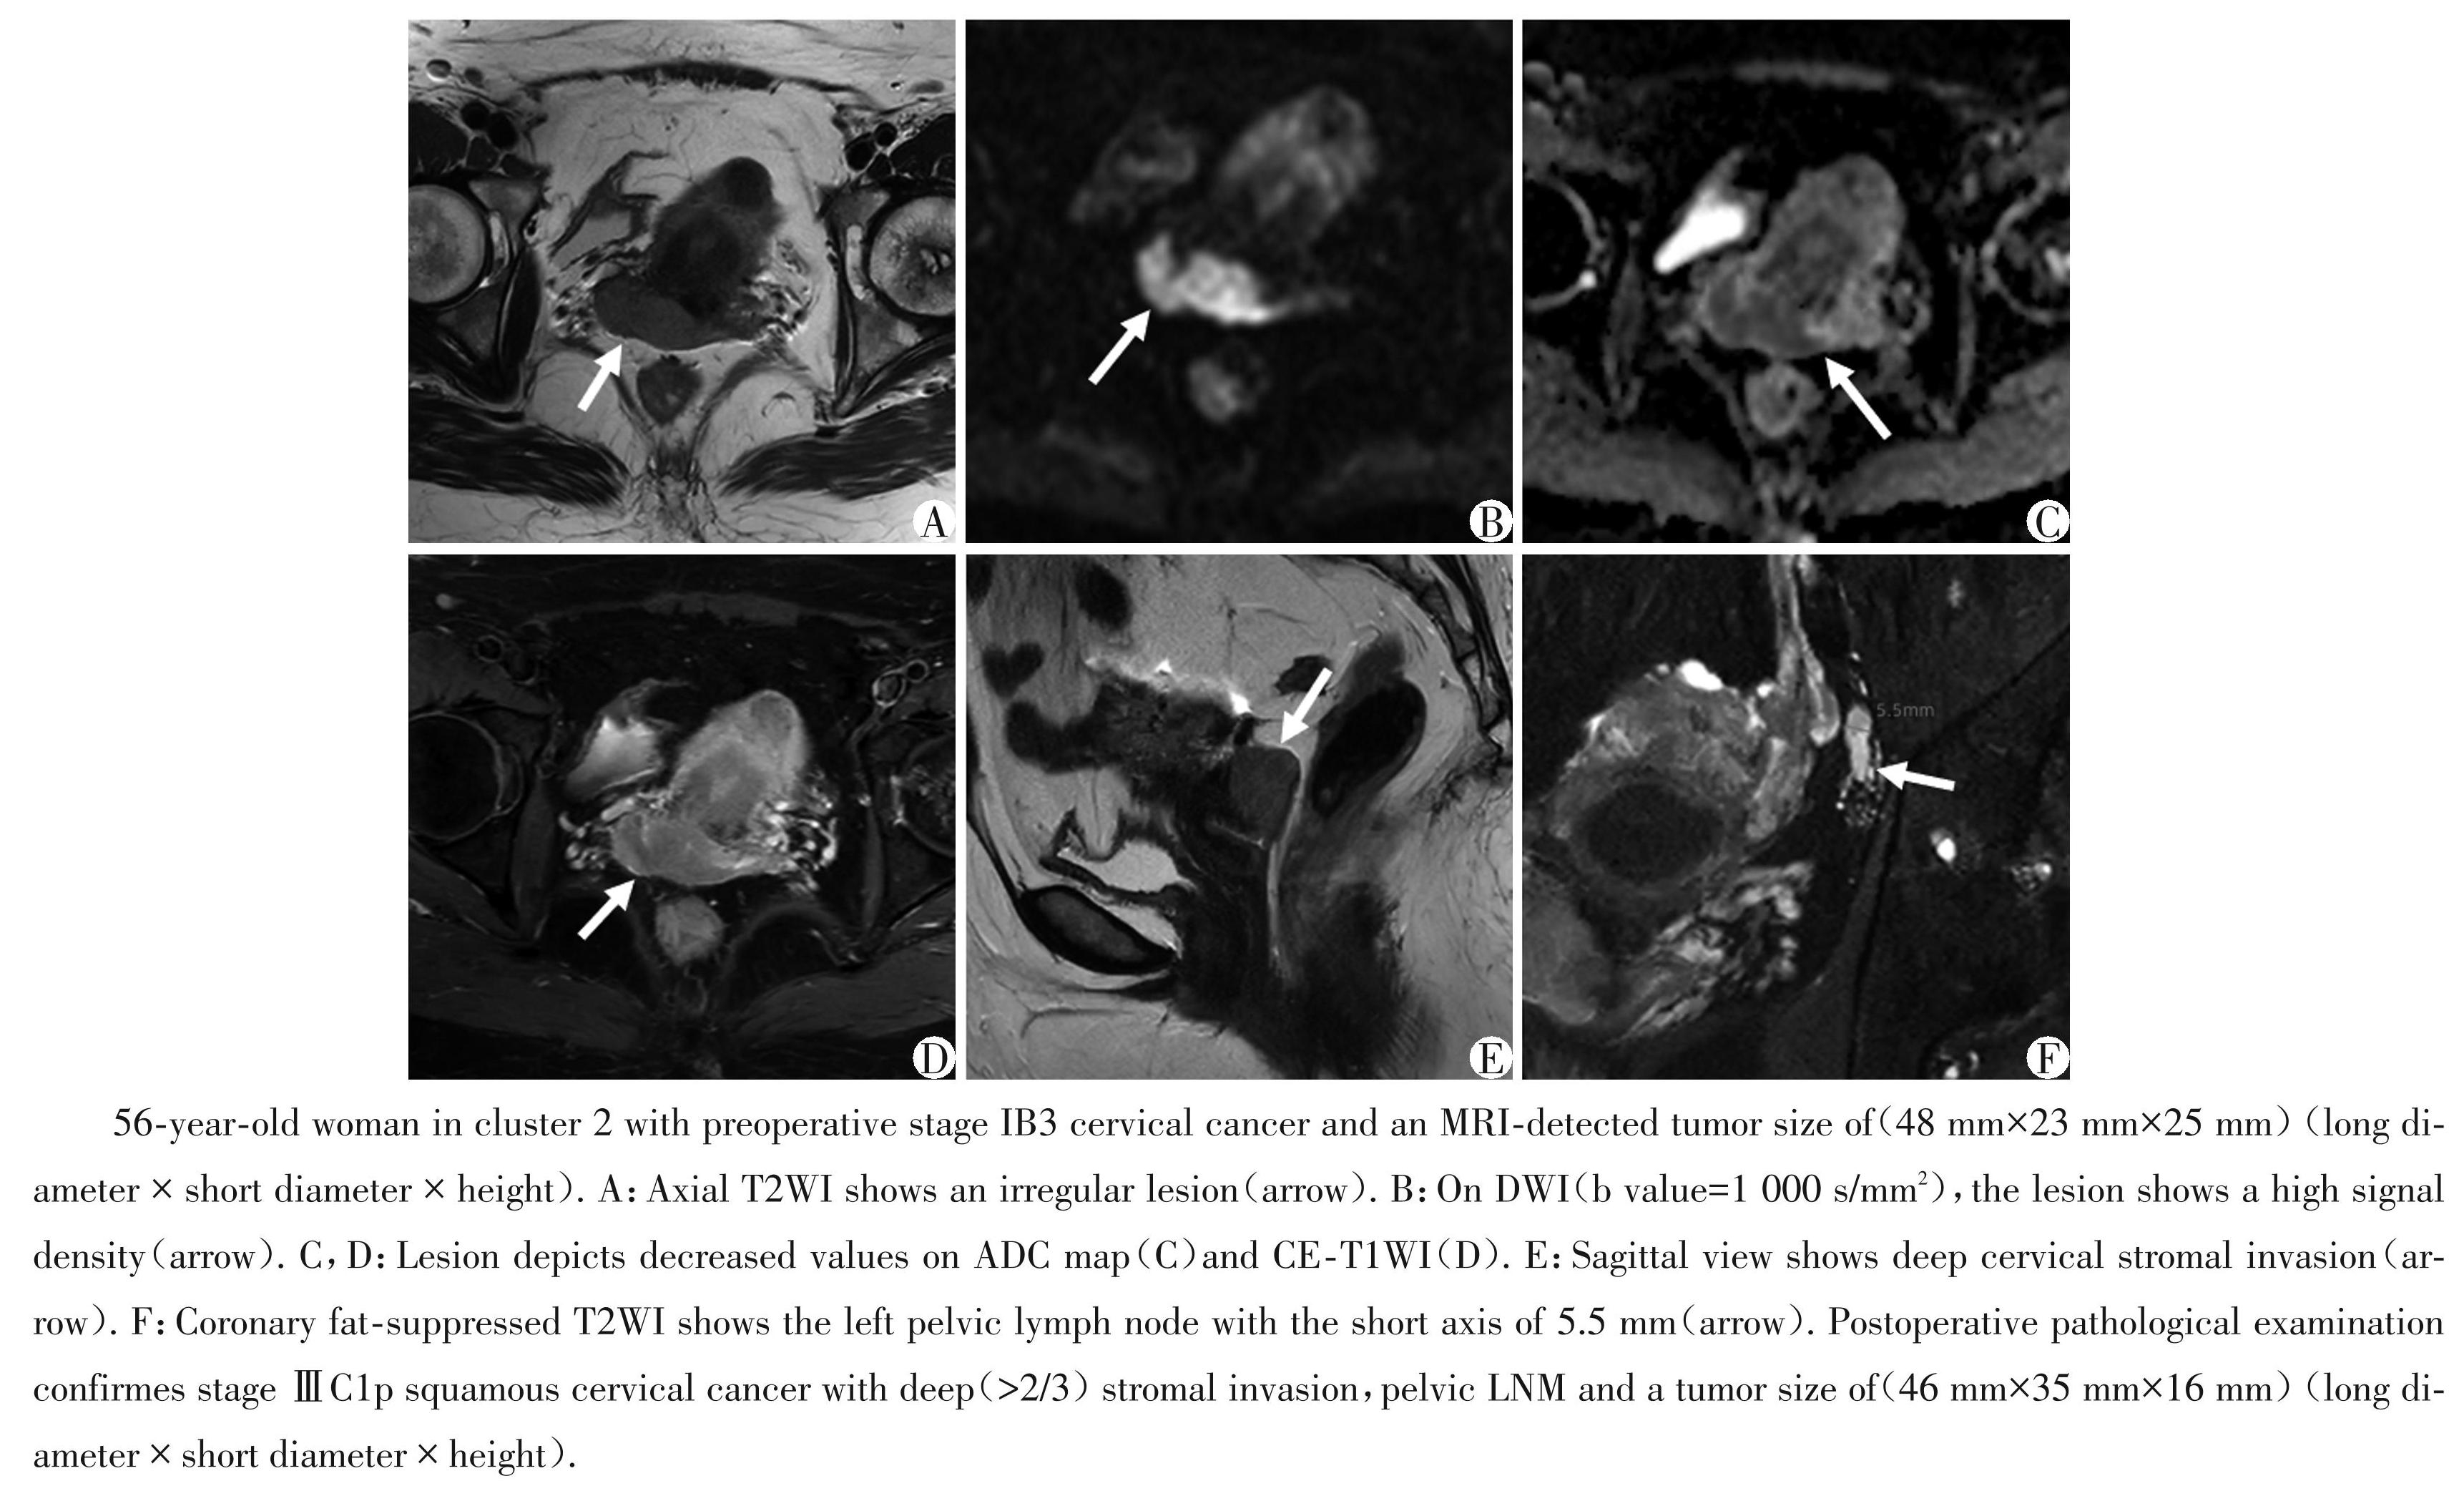

图4组2中的肿瘤具有较高临床及组织病理高危因素的典型病例

Figure4Typical case of a tumor in cluster 2 with higher risk clinical and histopathological high⁃risk factors

根据聚类预测指数和差距统计量,选择k=2作为最佳聚类数,最终将患者分为两组。表2总结了基于肿瘤的聚类分析结果以及两组间临床及组织病理学特征比较。结果显示,组 1 和组 2 之间在年龄(P=0.450)、组织学类型(P=0.665)、肿瘤分化程度 (P=0.440)、淋巴血管间隙侵犯(P=0.583)以及宫旁浸润(P=0.794)方面无统计学差异。组2的92例患者的 FIGO 分期晚于组 1,其中 Ⅲ Cp 期 30 例 (32.6%),ⅡB期1例(1.1%),ⅡA期25例(27.2%),而组1的患者大多为ⅠB期[50/72(69.4%)vs.36/92 (39.1%),P=0.001]。组2患者中30例(32.6%)存在盆腔淋巴结转移,这与FIGO ⅢCp期的患者数量相同,因为根据2018 FIGO指南,术后病理学证实存在盆腔淋巴结转移的患者被归为ⅢCp期,而组 1中只有9例(12.5%)淋巴结转移的患者,差异有统计学意义(P=0.002)。组2患者的肿瘤直径也明显大于组1 [短径:(28.38 ± 9.73)mm vs.(16.67 ± 6.32)mm,长径:(34.34 ± 9.72)mm vs.(21.02 ± 7.39)mm,高度: (29.92 ± 10.61)mm vs.(18.93 ± 8.01)mm,P 均 <0.001]。对于间质浸润深度,组 2 中宫颈间质浸润超过全层2/3的比例率明显高于组1[62/92(67.4%) vs.26/72(36.1%),P <0.001]。相比之下,组1中间质浸润深度在全层1/3~2/3以及<全层2/3的概率高于组 2[<1/3:13/72(18.1%)vs.10/92(10.9%):1/3~2/3: 33/72(45.8%)vs.20/92(21.7%),P 均<0.001]。图3和图4分别展示了每组的一个典型病例。